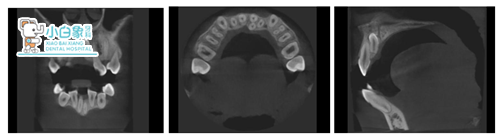

治疗前CBCT

X线见21根间高密度异常影像

见18、28、38、48恒牙

多生牙(埋伏阻生)